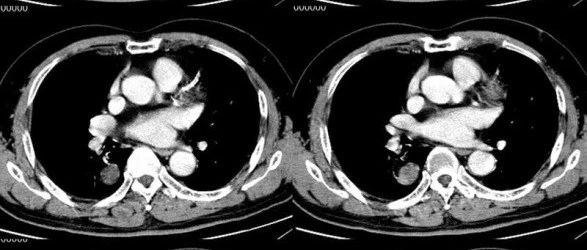

双侧卵巢畸胎瘤!

医学影像  yxyx-app  医学影像APP,打造伴随医生快速成长的影像学习社区。与影像园(Xctmr.com)一起提供最全面的影像案例库、基础(解剖、病理、影像诊断)知识、影像技术及考题等,为医生提供最佳的医学影像参考。【所属科室】普外科【基本资料】患者,女,71岁【主诉】B超发现盆腔肿块一天【影像图片】【讨论问题】如何诊断?【医学影像APP用户讨论】评论:...